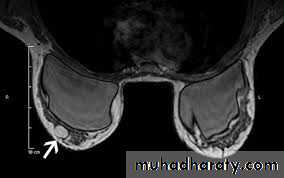

(3)magnetic resonance imaging (MRI); MRI is of increasing interest to breast surgeons in a number of setting: it can distinguish scar from recurrence in women who have had previous breast conservation therapy for cancer. It is the best imaging modality for the breast of women with implants. It has proven to be a useful as screening tool in a high risk women because of a family history. It is less useful than ultrasound in the management of the axilla in both primary breast cancer and recurrent diseases.